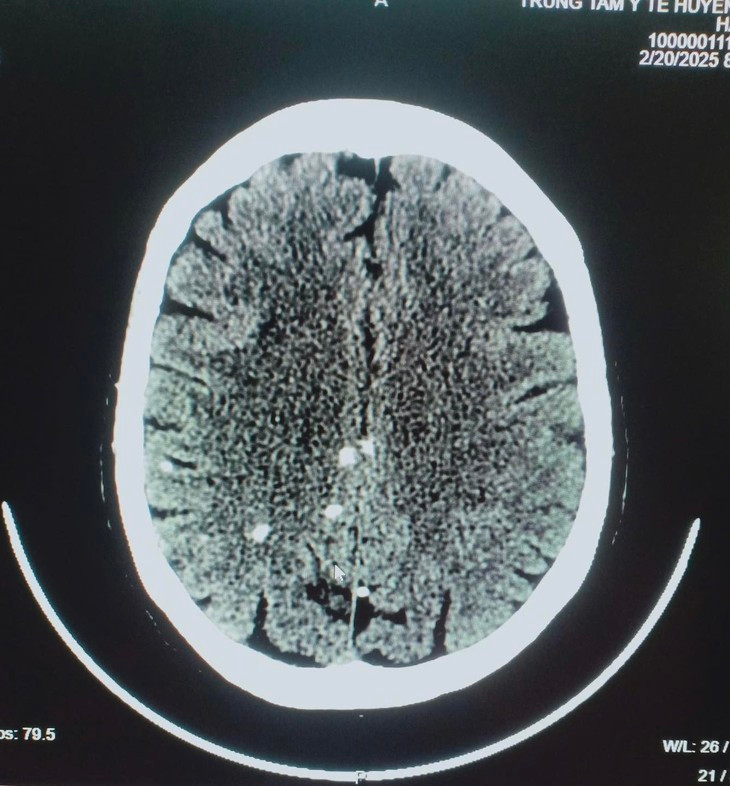

| Chi chít sán trong não bệnh nhân. Ảnh Trung tâm Y tế huyện Tân Sơn |

Bệnh sán não xảy ra khi kén sán có ở não từ một đến nhiều ổ. Mức độ tổn thương nặng hay nhẹ phụ thuộc vào số lượng kén sán có trong não. Biểu hiện thường gặp là: bệnh nhân bị nhức đầu, buồn nôn hoặc nôn, cơn co giật (động kinh), liệt nửa người hoặc tê bì rối loạn cảm giác, khó ngủ hoặc mất ngủ, mờ mắt, tăng áp lực sọ não, suy nhược thần kinh, rối loạn tâm thần, bệnh nhân có thể bị đột tử.